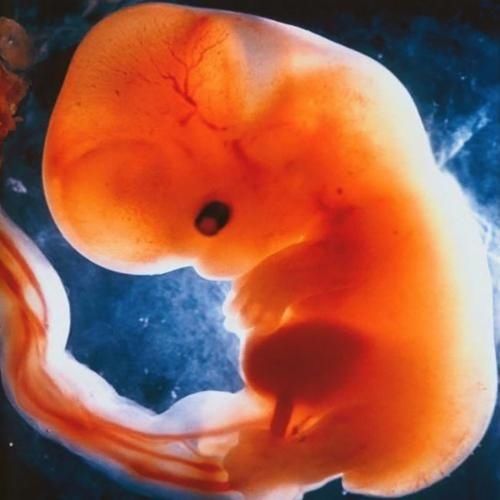

卵黄囊【 早期|怀孕早期这4项过关了,说明宝宝已经安家了,可以放心了】卵黄囊在妈妈怀孕5周的时候就可以看到了,最晚的也就在6周,如果一直没有出现的话,说明胚芽发育的不稳定,存在流产的风险。

卵黄囊主要的存在是在胚胎发育的早期,由它提供营养成分,在10周的时候慢慢地小时,所以在7周以后胎盘会代替的它的工作。

胎芽胚芽通常在怀孕5-8周可以看到,如果在8周以后还是没有看到胚芽的话,就会有问题。当然也有很多个例,我经常在抖音上看到很多妈妈虽然在b超没有看到胚芽,不愿意放弃孩子,等了1个月,胚芽回来了,但是这真的是赌,所以建议还是听医生的比较好。